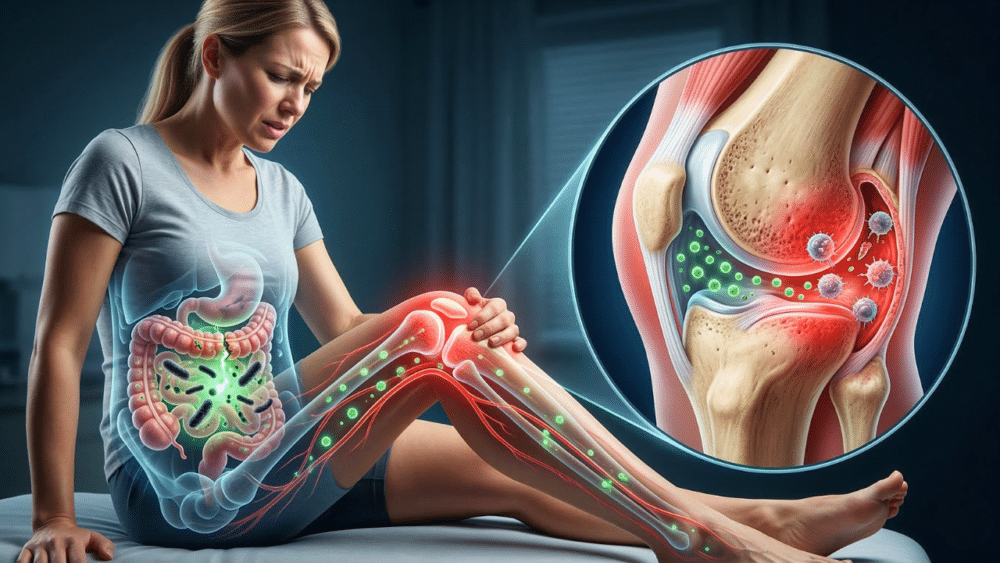

Imagine the lining of your intestines like a tightly woven mesh. Their job is to allow nutrients to pass into the bloodstream while keeping harmful substances — such as undigested food particles, bacteria, and toxins — out. In a healthy gut, this works perfectly. But when you have Leaky gutthe connections in that network become loose. This is called intestinal hyperpermeability.

When the gut microbiome is out of balance (a condition called dysbiosis), some harmful bacteria can multiply. These bacteria produce toxins called lipopolysaccharides (LPS). This LPS is particularly bad because it can break down the glue that holds intestinal cells together. This creates gaps, allowing LPS and other bacteria to leak directly into the bloodstream. Your body’s first line of defense has been compromised.

3. The toxic journey: from your gut to your joints

Once these bacterial toxins reach the blood, the liver, the body’s main detoxification organ, attempts to filter them out. But our modern, highly processed, high-carb diet puts the liver under constant stress. It gets exhausting. When the liver can’t keep up, these toxins spread freely throughout the body, leading to a chronic, low-grade inflammatory condition called metabolic endotoxemia.

Here’s the important part for your knees: These LPS toxins have a special affinity for the synovial capsule, the tissue that lines and lubricates the knee joint. They accumulate there, and your immune system, sensing the presence of a foreign invader, launches an attack. The problem is that it cannot distinguish between the poison and your tissue. It begins by attacking the synovial capsule itself. This is an autoimmune process. Your body causes inflammation, redness, and pain in your knee. We call it “wear and tear”.